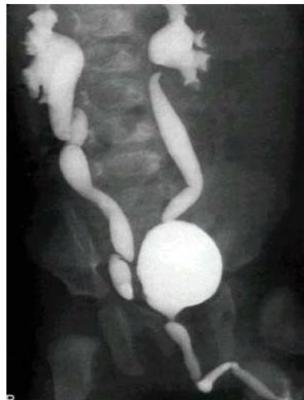

Vesicoureteral Reflux (VUR)

History:

- Recurrent UTIs

Modality:

- MCUG (micturating cystourethrogram)

Findings:

- Posterior urethral valve

- Dilated ureters

- Tortuous ureters

- Dilated ureteric pelvis bilaterally (hydronephrosis)

Posterior Urethral Valve (PUV)

- MCUG / VCUG (voiding cystourethrogram) only in boys

- Dilated proximal urethra

- Dilated ureter

- Dilated bladder

- Dilated posterior urethra

Only in boys